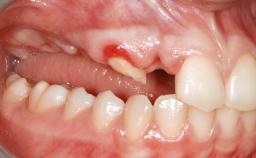

A 20-year-old woman was referred for implant therapy in 2004. Her medical history revealed no significant findings, and neither did she smoke nor take any medications. An extraoral examination revealed no abnormalities of the skin, hair or nails. The intraoral examination revealed only 11 permanent teeth clinically. These were normal in shape, size, and color. In addition, eight retained deciduous teeth (53, 62, 63, 71, 72, 73, 81, 82) were present. No abnormalities were detected during the general examination. The family history revealed that the patient’s father and two sisters were on record with similar conditions. The clinical examination revealed a thick gingival biotype. No recession of the attached gingiva was noted, but the retained deciduous teeth were mobile and unsightly. As a syndrome had not been diagnosed, the case was categorized as non-syndromic oligodontia.

Width of Edentulous Span 1 tooth (>= 7 mm) 1 tooth (< 7 mm) 2 teeth or more

Bone Volume Horizontally and vertically sufficient Horizontally deficient Deficient vertically or deficient vertically AND horizontally